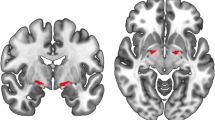

At an uncorrected voxel-level threshold of p < 0.001, mu was negatively correlated with numerous clusters in widespread parts of the brain including bilateral occipital, frontal, and temporal cortices (see Fig. 3 and Supplementary Table S7). Two larger clusters in right frontal and left temporal regions survived correction for multiple comparisons. Sigma was negatively correlated with grey matter volume in right frontal pole and left supramarginal gyrus (after correction for multiple comparisons), and smaller clusters in left temporal and frontal regions, and the precuneus. There was a positive correlation between sigma and grey matter volume in bilateral temporal gyri and the cerebellum. Tau was negatively correlated with clusters in the right cerebellum.

Correlations between ex-Gaussian parameters and grey matter (GM) and white matter (WM) volume for contrasts with clusters that survived multiple comparison correction. Clusters of significant correlations are overlaid on the MNI standard brain in radiological convention, i.e., the right side of the image corresponds to the left hemisphere. See Supplementary Tables S6 and S7 for all uncorrected clusters

There were two larger clusters of negative correlation between sigma and white matter volume in left temporal gyrus that survived multiple comparison correction (see Fig. 3 and Supplementary Table S7). At an uncorrected voxel-level threshold of p < 0.001, mu was negatively correlated with white matter volume in middle temporal regions and tau was negatively correlated with white matter volume in left lingual regions.